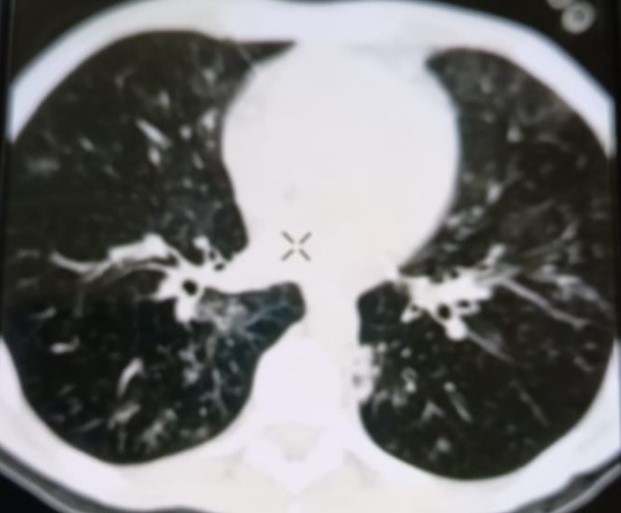

При проведении рентгенологического исследования органов дыхания в динамике спустя 2 недели с момента начала терапии данные компьютерной томографии высокого разрешения указали на следующие изменения: на фоне очаговой диссеминации в легких значительно увеличились по площади участки "матового стекла" в верхних долях обоих легких (описанные зоны неоднородные, сливные); площадь поражения легочной ткани - около 35-40%. В средних и нижних отделах легких с двух сторон выявлялись многочисленные перибронхиальные очаги до 3 мм в диаметре по типу «дерево в почках». В S 6 справа определялась зона альвеолярной инфильтрации. Выпот в плевральных полостях не определялся; внутригрудные лимфоузлы не увеличены. Заключение: признаки двусторонних полисегментарных интерстициально-инфильтративных, диссеминированных мелкоочаговых изменений легких, средняя вероятность вирусной пневмонии (в том числе COVID-19), в сочетании с диссеминированным процессом в легких (рис. 1-4).

Рисунок 1

Рисунок 2

Рисунок 3

Рисунок 4

Рис. 1-4. Компьютерная томограмма пациента Т., с ВИЧ: чередование участков «матового стекла» с диссеминированным процессом, инфильтрацией легочной ткани справа, наличие симптома «дерево в почках» (респираторный бронхиолит).